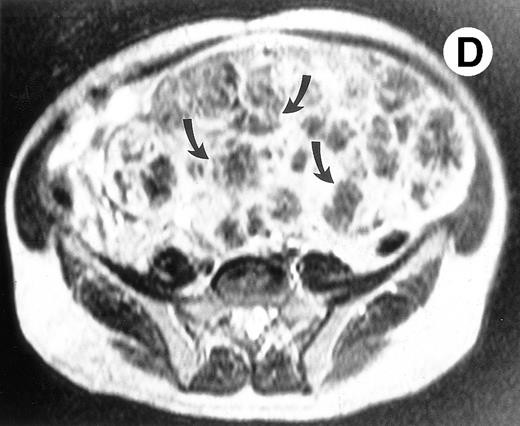

Surgical pathology showed a 6.5-kg spleen with nodular appearing external surfaces and focal subcapsular infarcts, ranging in size from 0.5 to 3.4 cm. Serial sections showed rubbery and focally fibrotic surfaces (Fig 2A). This correlated with his presurgical axial T2-weighted MRI, which demonstrated multiple low signal intensity nodules not seen on T1-weighted views (Fig 2B through D). Although MRI is useful in monitoring response to therapy, this case demonstrates that volumetric measurements alone may not be adequate, especially when there are multiple areas of decreased signal intensity on T2-weighted STIR images. Both splenic nodules and infarcts are common in Gaucher patients, occuring in approximately 30% and 32% of patients, respectively.5 Thus, the volume free of nodules and infarct may be a more reliable measure of response to enzyme therapy in these patients.

(A) Photograph of the patient's spleen showing multiple nodules (arrows) with area of subcapsular infarcts (curved arrows). (B) Coronal STIR MR image of the (L) liver and spleen (IR 2450/100/30) shows multiple low signal intensities nodules (curved arrows) in the enlarged spleen. (C) Axial T1-weighted (SE 300/10) MR image shows splenomegaly with no focal splenic signal abnormality. (D) Axial T2-weighted (SE 4293/80) MR image of the spleen at the same level as (C) shows multiple low signal intensity nodules in the enlarged spleen (arrows).